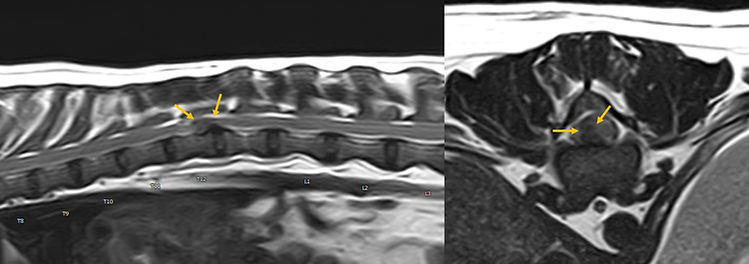

MRI

자기공명영상

MRI로 확인할 수 있는 질환

MRI는 특히 신경계 질환 진단에 강점을 가지고 있습니다.

뇌수막염

후두골이형성 및 척수공동증

디스크 탈출증